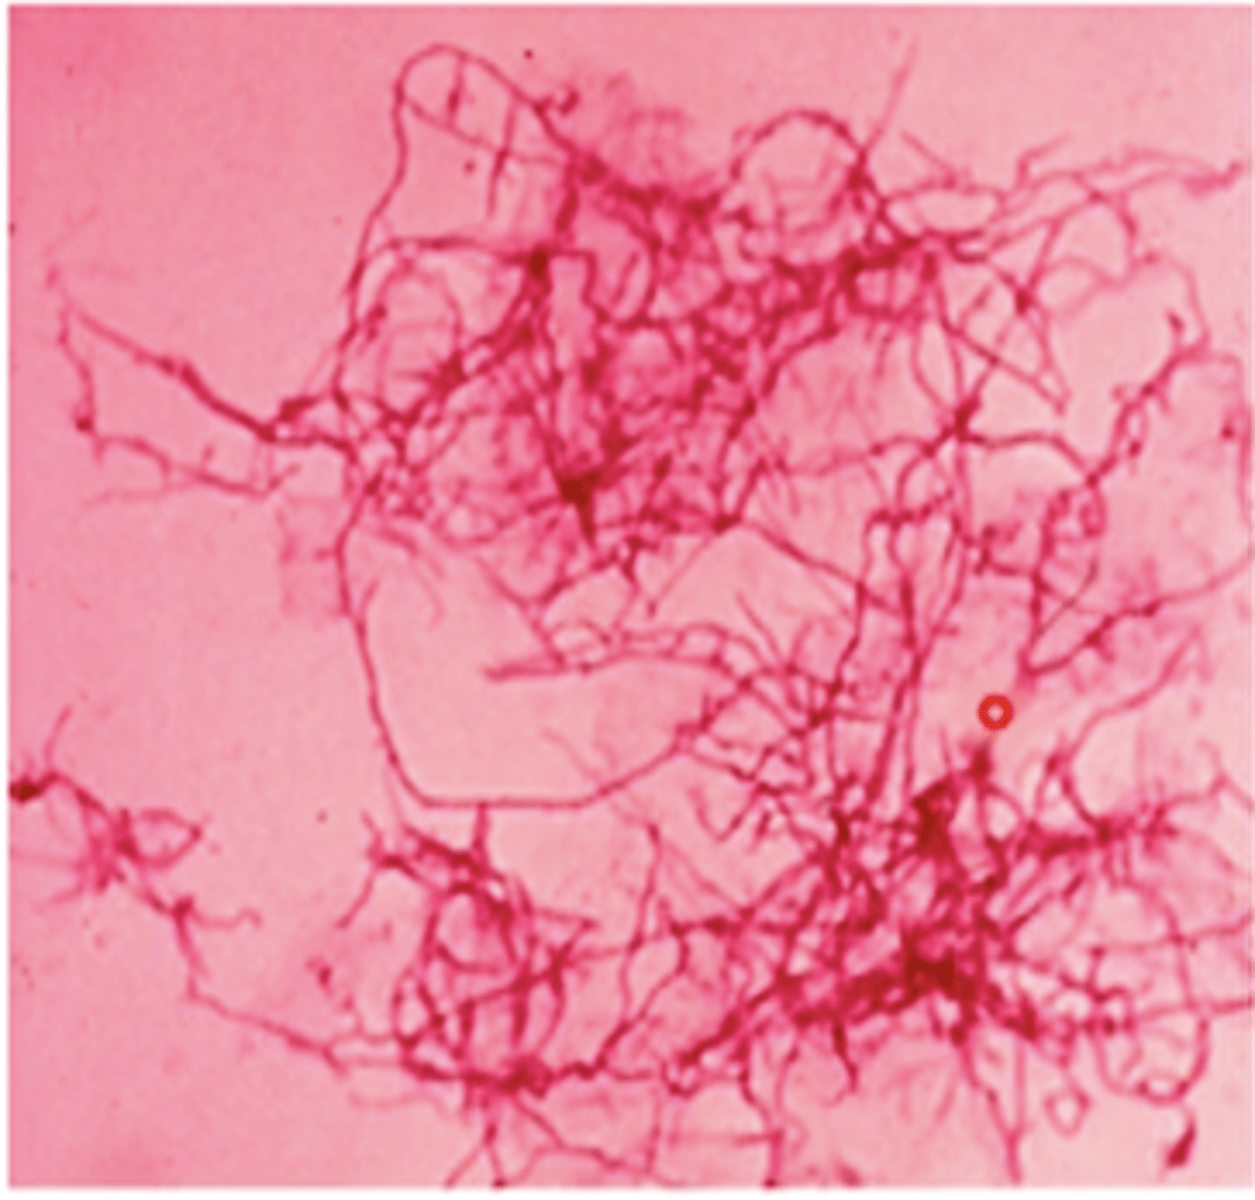

- branching filaments

- produces flagellated (motile) spores

Dermatophilus congolensis

- dermatophilosis

- trauma/persistent wetting facilitate invasion of epidermis and hair follicles

exudative dermatitis with formation of scabs/crusts

- paintbrush lesions of matted hair